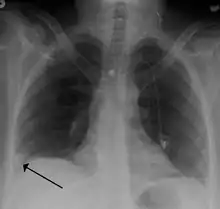

صورة الصدر الشعاعية

تستخدم هذه التقنية لنفي وجود أي مرض صدري آخر كذات الرئة أو استرواح الصدر أو أي كسر في عظام القفص الصدري،